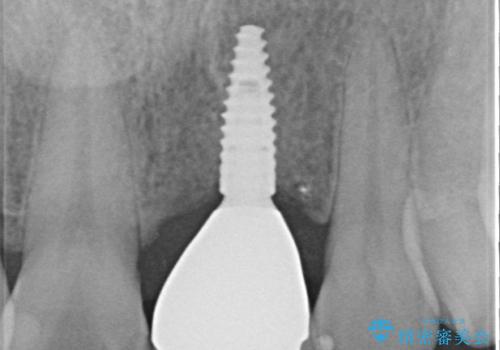

歯茎に溝が 大きく欠損した前歯のインプラント補綴治療

- 歯が朽ちてしまい、歯茎に大きな溝ができていることを気にして来院された患者様です。

インプラント治療を希望されておりましたが、軟組織の欠損が非常に大きいため、骨の回復を待ちながら歯肉の形態を整えていくこととしました。

歯肉形態を概ね回復するタイミングでインプラントを埋入し、補綴治療を行うこととしました。

骨の前後幅が小さかったため、細いインプラントを選択せざるを得ない状況でした。咬合力が非常に強い方のため、就寝時のマウスピース装着を徹底していただき、インプラントへの負担を軽減することとしています。